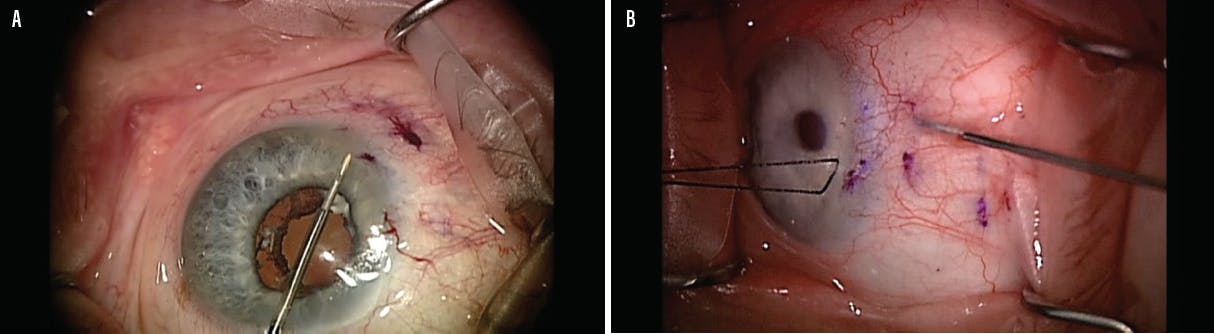

In 2016, the FDA approved the Xen Gel Stent (Allergan) for the treatment of patients with refractory glaucoma in whom previous surgical treatment failed and patients who have primary open-angle glaucoma or pseudoexfoliative or pigmentary glaucoma with open angles who are unresponsive to maximum tolerated medical therapy (see Putting the Xen Gel Stent to the Test).7,8 The device comes preloaded in an injector. It is implanted through a clear corneal incision using an ab interno approach (Figure 4A). The Xen shunts fluid from the anterior chamber to the subconjunctival space, forming a low-lying bleb.7,8

Recently, many surgeons have transitioned to ab externo placement of the Xen Gel Stent (Figure 4B). Although techniques vary, the greatest advantage of an ab externo approach is that it avoids entangling the device in sub-Tenon capsule, which can increase the rate of bleb needling.